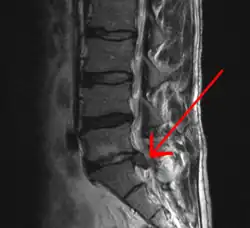

The straight leg raise test can detect pain originating from a herniated disc. When warranted, imaging such as MRI can provide clear detail about disc related causes of back pain (L4–L5 disc herniation shown)

Imaging is indicated when there are red flags, ongoing neurological symptoms that do not resolve, or ongoing or worsening pain.[5] In particular, early use of imaging (either MRI or CT) is recommended for suspected cancer, infection, or cauda equina syndrome.[5] MRI is slightly better than CT for identifying disc disease; the two technologies are equally useful for diagnosing spinal stenosis.[5] Only a few physical diagnostic tests are helpful.[5] The straight leg raise test is almost always positive in those with disc herniation.[5] Lumbar provocative discography may be useful to identify a specific disc causing pain in those with chronic high levels of low back pain.[44] Similarly, therapeutic procedures such as nerve blocks can be used to determine a specific source of pain.[5] Some evidence supports the use of facet joint injections, transforminal epidural injections and sacroilliac injections as diagnostic tests.[5] Most other physical tests, such as evaluating for scoliosis, muscle weakness or wasting, and impaired reflexes, are of little use.[5]